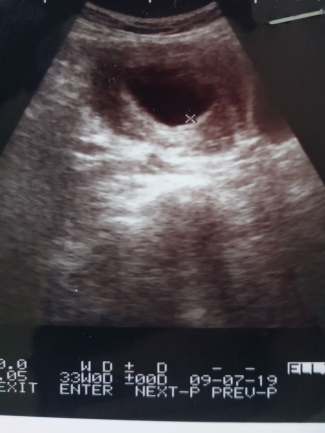

Artinya ada duakemungkinan yang bisa terjadi pertama janin akan tumbuh da berkembang menjadibayi dan kedua adalah janin tidak berkembang dan akhirnya mati keguguran. Berikut ini penyebab jani tidak berkembang yang harus diketahui ibu hamil diantaranya saat usia kehamilan 5 minggu janin bunda sebenarnya sudah agak terlihat. Biasanya janin yang tidak berkembang ini terdeteksi ketika ibu hamil melakukan pemeriksaan usg. Mengidam dimana ibu hamil muda menginginkan makanan yang terkesan tidak umum seperti ingin konsumsi makanan yang sebelum tidak disukainya. Tanda tanda kehamilan yang kuat. Suhu basal dimana setelah ovulasi tetap dalam kondisi tinggi antara 372 378 derajat.

Sedangkan pada kehamilan dengan janin yang tidak berkembang ibu tidak merasakan adanya gerakan janin sama sekali di dalam rahimnya. Bila detak jantung kurang terdengar pada tes pertama dan tidak terdengar detak jantung lagi di tes berikutnya ini adalah tanda janin tidak berkembang. 9 tanda janin tidak berkembang paling akurat yang membantu ibu hamil segera meminta pertolongan medis dan menurunkan resiko masalah kesehatan ibu hamil. Anda tidak dibenarkan menyiar artikel ini di mana mana laman web atau status facebook yang lain tanpa pemberian kredit dan pautan yang tepat lagi berfungsi pada artikel asal di laman theasianparent malaysia.